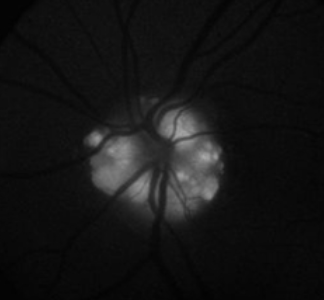

• This image shows optic nerve head drusen displaying autofluorescence.

• Optic disc drusen can have autofluorescence due to the presence excessive mitochondria in these drusen that contain porphyrins.

• Retinal astrocytic hamartomas may also show autofluorescence.